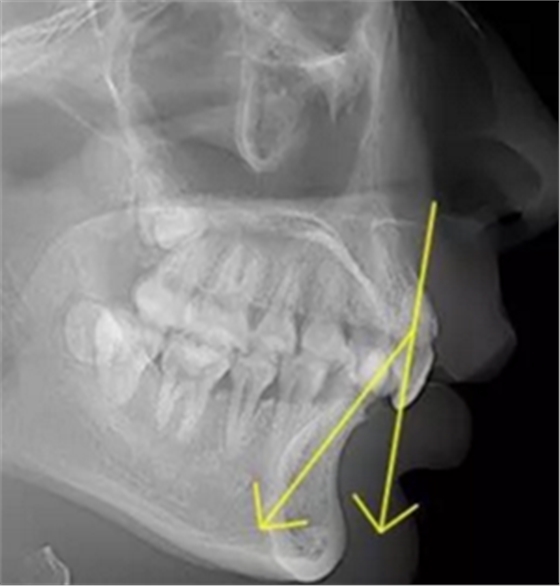

正常情況下,我們的上前牙是蓋在下前牙唇側(cè)3mm內(nèi)的,上下切牙牙軸交角為125°左右,

正常前牙交角